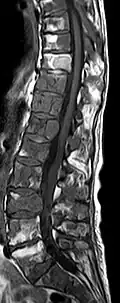

- Vergleich CT / MRT bei osteolytischen Metastasen eines Mammakarzinoms in der Wirbelsäule

Sagittale native T1-gewichtete MRT -

Sagittale native T1-gewichtete MRT. Deutlich sichtbar die Ausdehnung bis in die Bogenwurzeln.